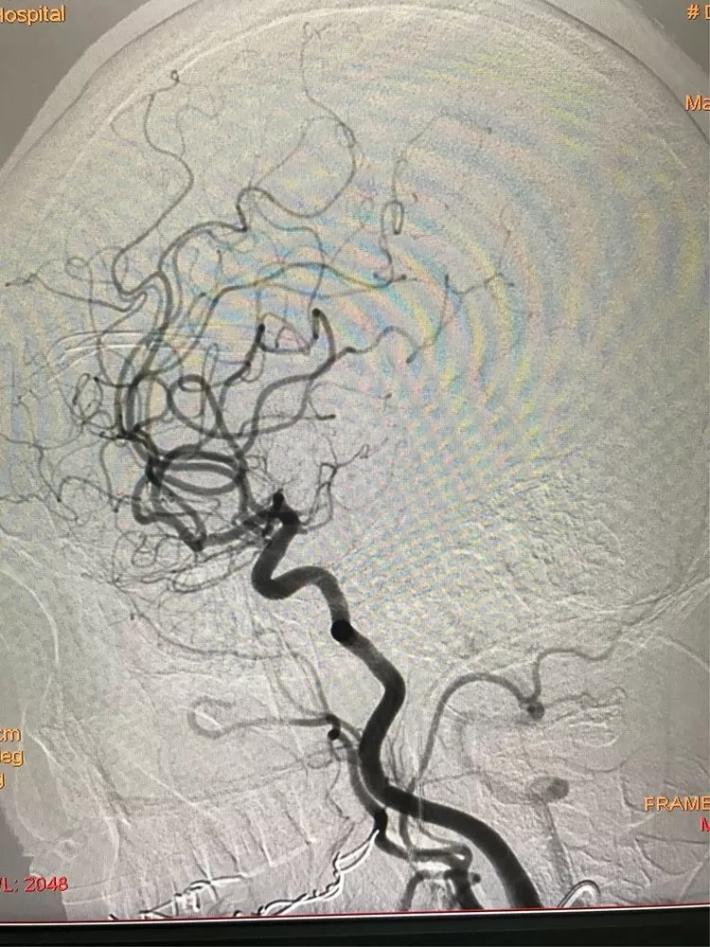

患者女性,64岁。主因突发右侧肢体瘫痪3.5小时急诊入院。颅脑CT:未见出血。Nihss评分18分。急行静脉溶栓,同时MRA检查。

MRA显示:左侧颈内动脉闭塞。

立即桥接取栓,造影显示:左侧颈内动脉闭塞。

右侧颈内动脉向左侧没有代偿。

椎动脉造影显示后交通动脉没有代偿。

微导管进入左侧大脑中动脉远端真腔。

置入支架。

可见大脑中动脉有血流。

取出支架未见血管开通。

再次置入微导管。

置入支架取栓。

见颈内动脉开通,大脑中动脉远端有血栓逃逸。